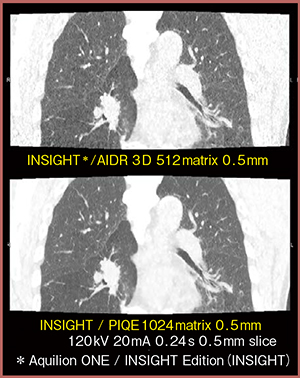

320列ADCT「Aquilion ONE / INSIGHT Edition」は,高精細技術と四次元動態技術を統合した最新装置である。超解像画像再構成技術「Precise IQ Engine(PIQE)」は,Aquilion PrecisionのSHRデータを教師データに使用し,1024マトリクス再構成が可能で,すりガラス濃度結節の内部構造や気管支を高精細に描出する。撮影後に後処理で適用できることは大きな利点であり,また,呼吸動態CT画像にも対応する。AIDR 3Dとの比較でも,微細構造や腫瘍の内部構造がより明瞭に描出され,臨床実用性が高い(図5)。

図5 超解像画像呼吸動態CT(肺がん症例)